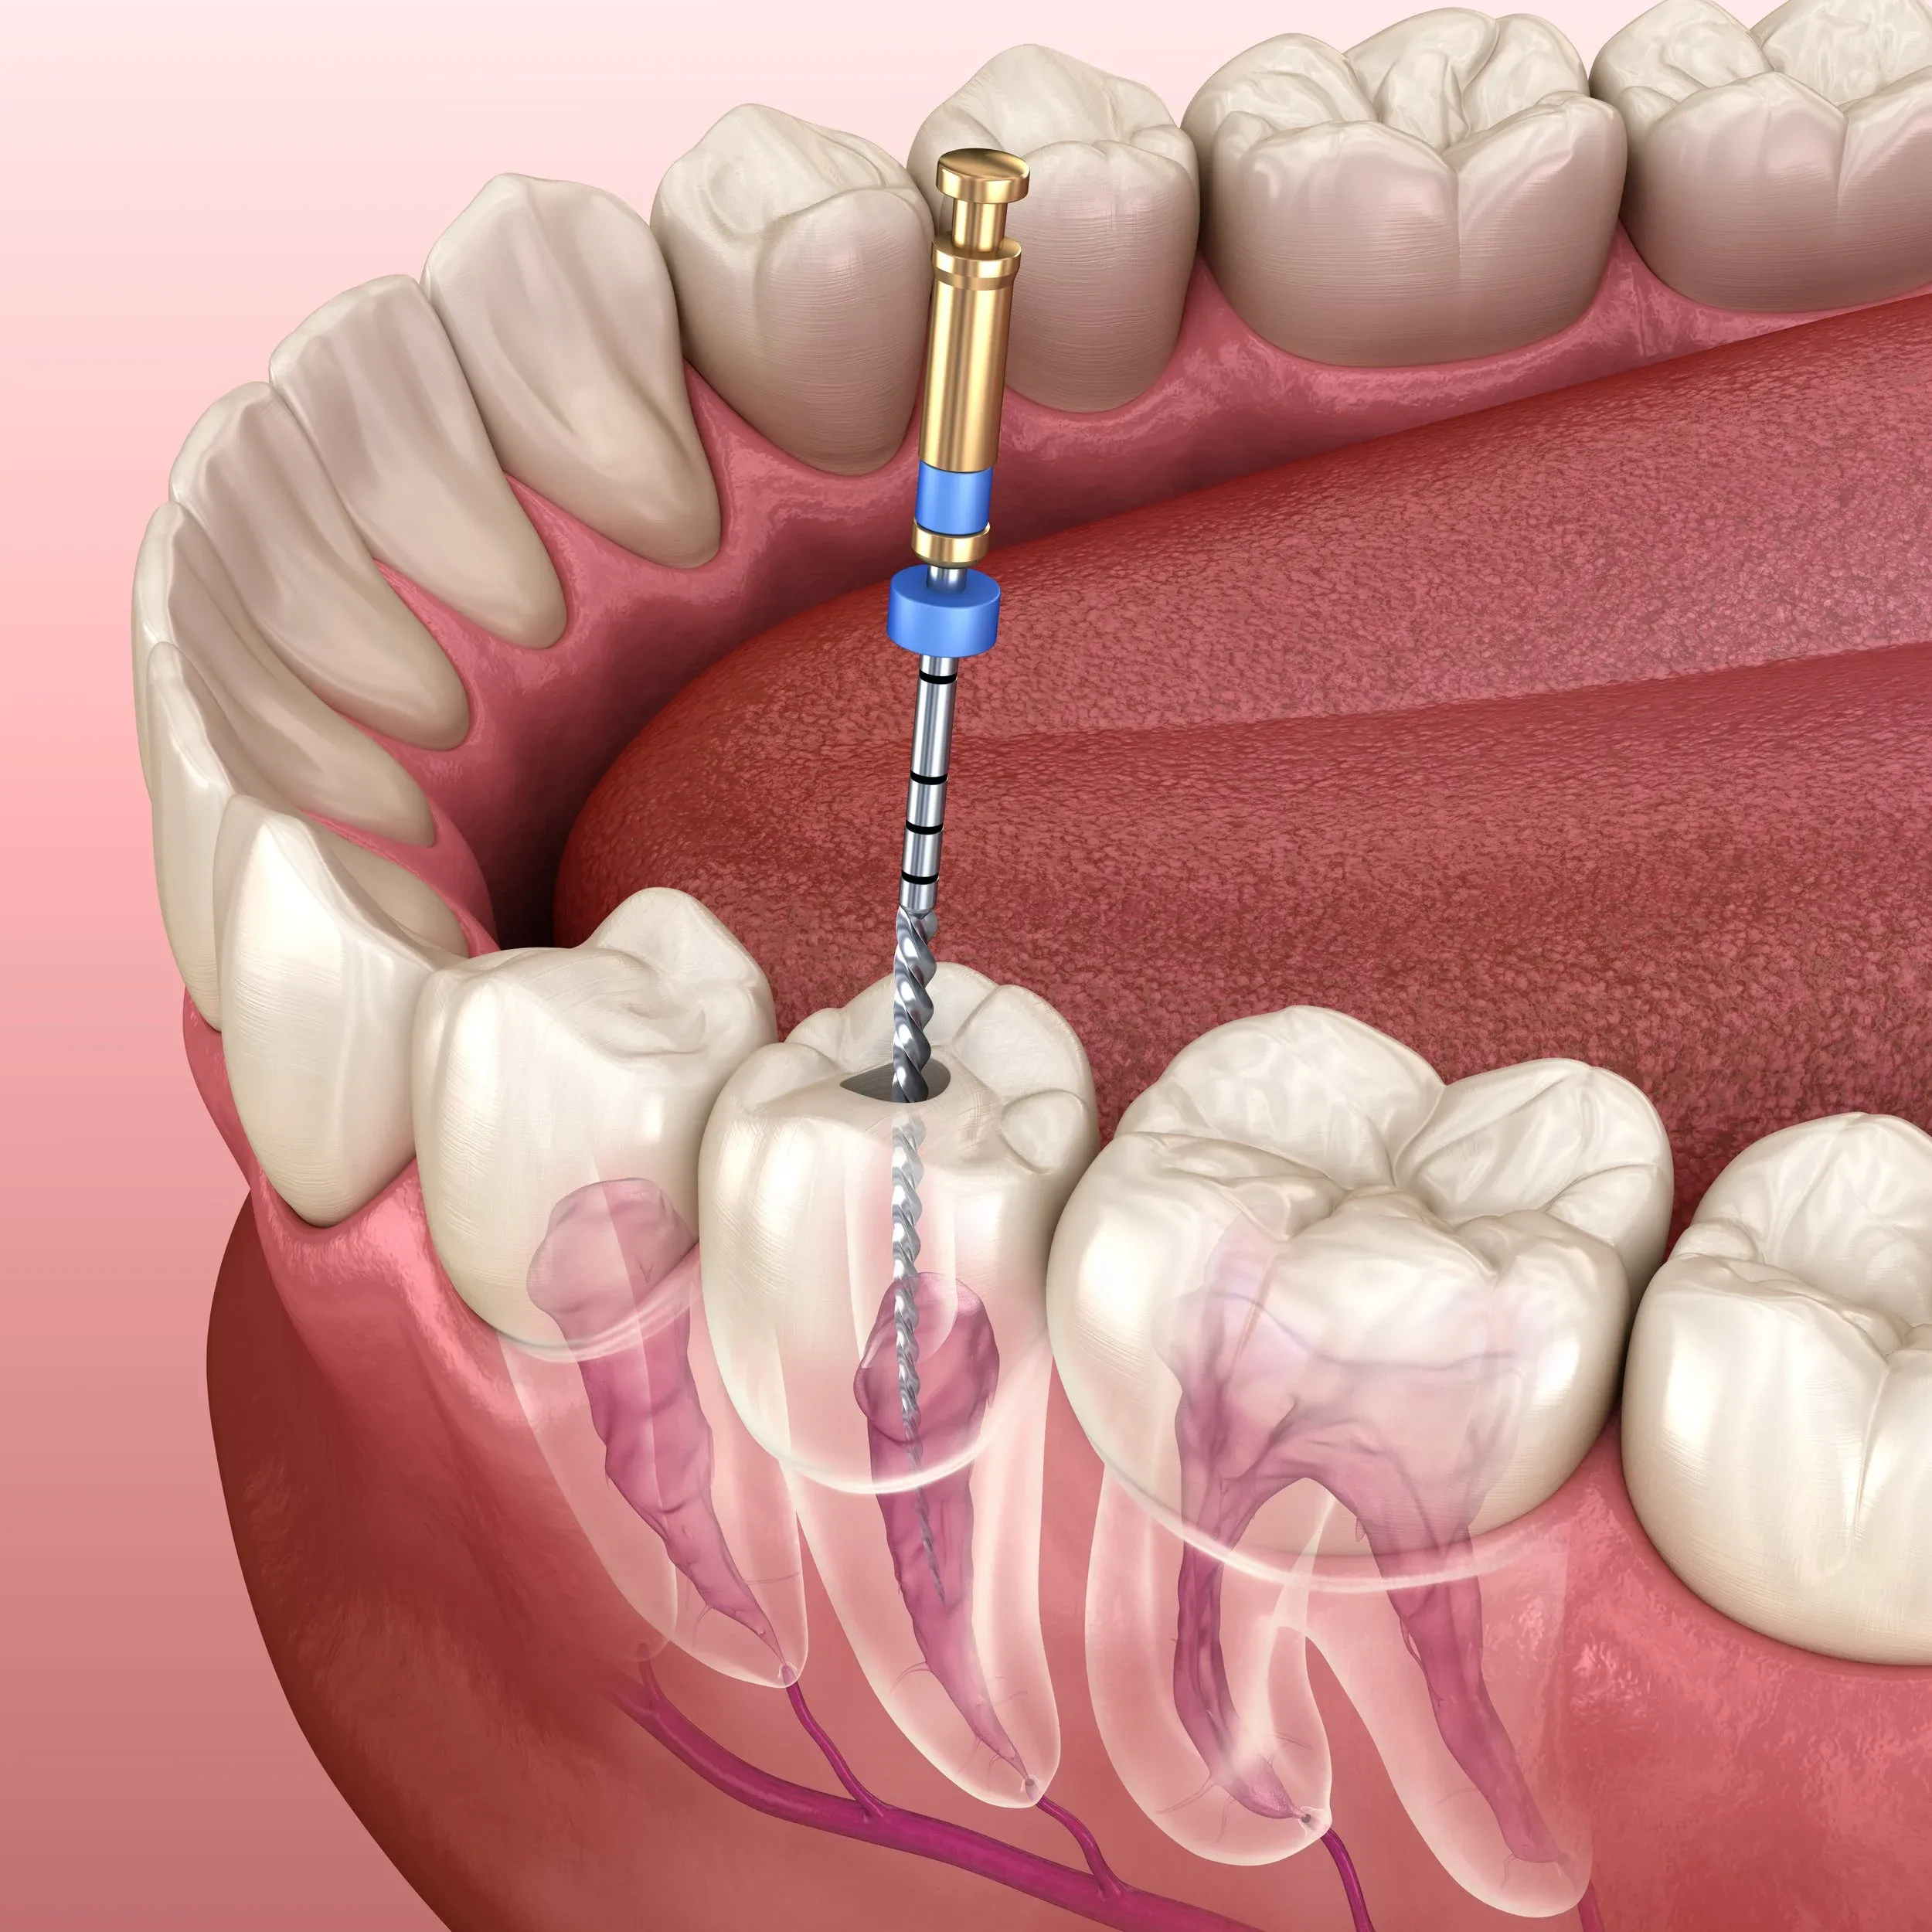

A bone graft is a procedure where the dentist adds bone or bone-like material to your jaw to create a solid foundation for dental implants or other oral treatments. Think of it as reinforcing the soil before building a house – if the foundation isn’t strong enough, the structure won’t stand securely. In dentistry, this is often necessary when the jawbone has shrunk due to tooth loss, gum disease, or injury.

### What to Expec

t During the Procedure

In Thailand, bone grafting for dental purposes usually takes place under local anaesthesia, although sedation is available if you feel anxious. The dentist will prepare the site, place the graft material carefully, and secure it so that it can integrate with your natural bone over time. The healing process can take several months, during which your dentist will monitor your progress closely.